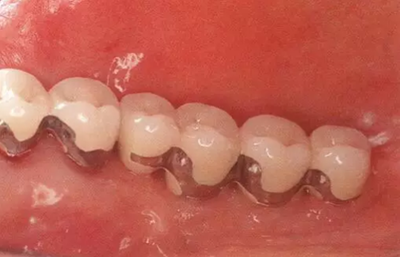

▲圖4-5,6

圖4-5 取模前的狀態(tài)。頰舌側角化齦充足。

圖4-6 佩戴最終修復體時的頰側面照。菌斑控制良好。